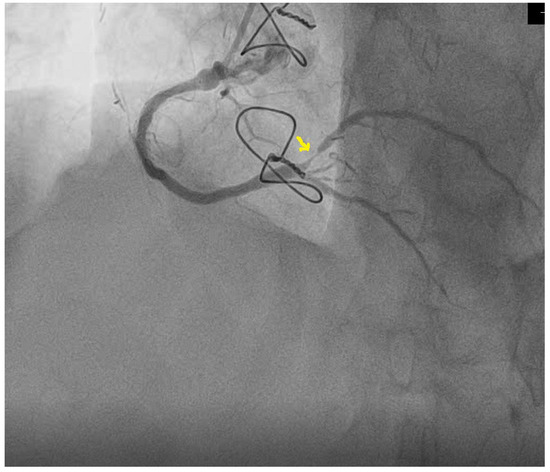

Considering the patient’s history, it was decided to perform coronary angiography, which showed multiple coronary stents, the right-dominant coronary system, and diffusely atheromatous coronary arteries; a LAD with ostial in-stent total chronic occlusion, but with a patent arterial graft on the mid segment; and an RCA with serial stenotic lesions of a maximum of 50–70% and a sub-occlusive lesion at the postero-lateral branch (PLB), as shown in Figure 5. Percutaneous coronary intervention was performed, and a 2.25–14 mm DES was implanted on the postero-lateral branch with a good final angiographic result (Figure 6).

Figure 5. Sub-occlusive stenosis of the postero-lateral branch of the right coronary artery (arrow).

Figure 6. Coronary angiography post dilatation and stent implantation in the postero-lateral branch of the right coronary artery (arrow).